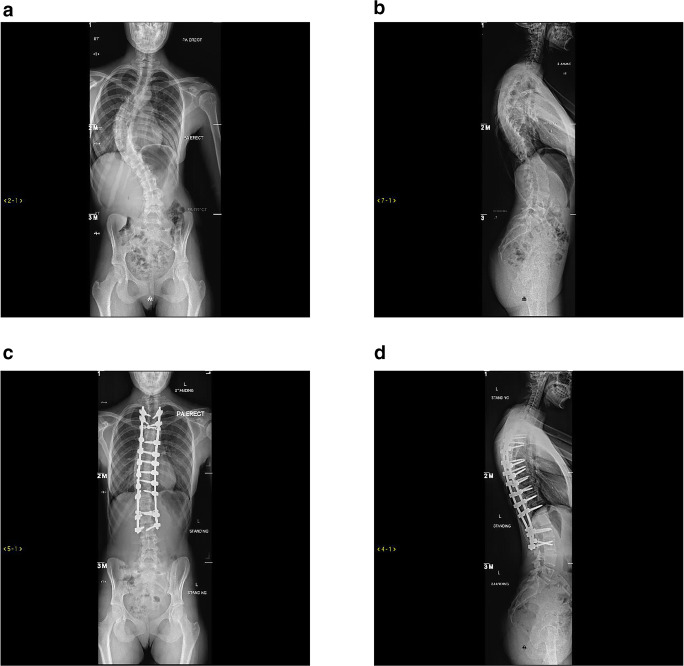

Whether or not an AIS patient should undergo surgical intervention depends on several factors including the overall curve size and pattern, curve progression and skeletal maturity. Surgery is considered in skeletally immature patients with structural thoracic curve Cobb angles over 40° or patients who show continued progression [56]. For over 100 years, fusion surgery has been used for the treatment of scoliosis [56]. Patients can undergo anterior spinal fusion (ASF), posterior spinal fusion (PSF) (Fig. 1) or a combined anterior/posterior approach. The outcomes and comparisons between these approaches are summarised in Table 1.

Fig. 1.

Posterior anterior and lateral preoperative radiographs of a female patient with adolescent idiopathic scoliosis (a, b) and postoperative radiographs after posterior surgical approach (c, d)